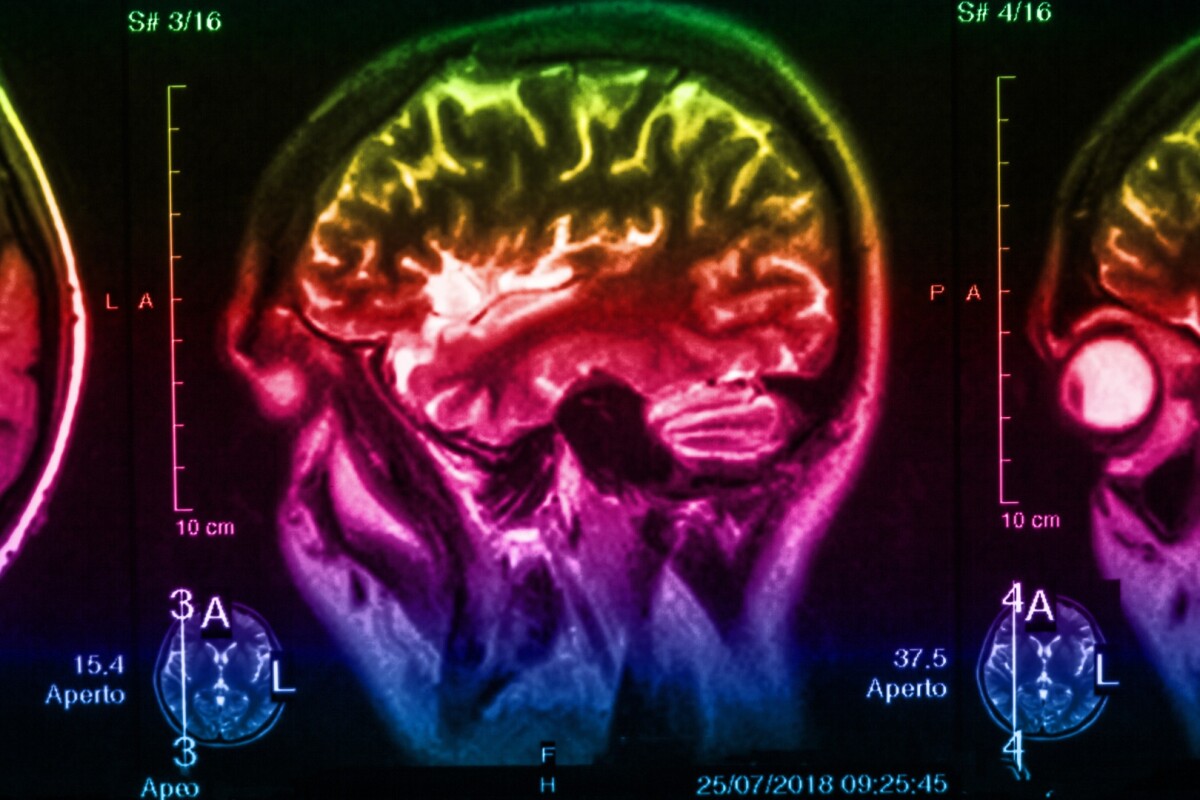

Parkinson s disease pd is a neurodegenerative disorder that affects predominately dopamine producing dopaminergic neurons in a specific area of the brain called substantia nigra.

Parkinsons disease brain. It causes nerve cells in a part of the brain called the substantia nigra to die. Parkinson s disease pd is a progressive neurological disease that affects the brain and body in different ways. Many of the symptoms are due to a loss of neurons that produce a chemical messenger in your brain called dopamine. Parkinson s disease is an illness that affects the part of your brain that controls how you move your body.

In parkinson s disease certain nerve cells neurons in the brain gradually break down or die. Parkinson s disease is a condition that causes the brain to become progressively more damaged over time said the nhs. Environmental pollutants pathogens viral or bacterial and genetics are some possible causes of the initiation of this disease process. When dopamine levels decrease it causes abnormal brain activity leading to symptoms of parkinson s disease.

This part of the brain is important for. Data from a five year clinical trial is adding to growing evidence that deep brain stimulation or dbs can slow the ravages of parkinson s disease. The disease process is thought to be multifactorial and much research has been done to attempt to uncover the cause. Parkinson s disease is a brain disorder that gets worse over time.

Parkinson disease pd also known as idiopathic parkinsonism is a neurodegenerative disease and movement disorder characterized by resting tremor rigidity and hypokinesia due to progressive degeneration of dopaminergic neurons in the substantia nigra. You could be at risk of the neurodegenerative condition if your voice changes. Symptoms generally develop slowly over years. Parkinson s is a condition that causes the gradual loss of the dopamine producing brain cells of the substantia nigra an area of the brain located just above where the spinal cord meets the.